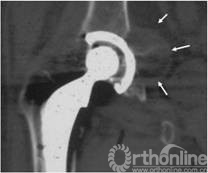

图6 CT片示髋臼假体上方DeLee和Charnley II区骨溶解, I、III区骨长入固定,髂窝内假性瘤样肉芽肿(箭头所示)

择期行双切口入路(髂腹股沟入路联合髋关节后外侧入路)右腹股沟炎性假瘤切除、骨溶解病灶清除、同种异体颗粒骨植骨、更换负重界面手术治疗。经髂腹股沟入路,见右髂窝内边界清楚,囊壁完整、质中等包块,切开囊壁,可见包块内黄色干酪样物(图7),清除干酪样物,完整切除包块囊壁,见囊壁基底位于髋臼内侧壁并与髋臼通过一直径约5mm骨缺损区相同。术后组织学可见异物吞噬反应(图8)切除髂窝炎性假瘤,经髂骨内板骨缺损区清除髋臼骨溶解病灶,同种异体颗粒骨打压植骨。髋关节后外侧入路更换高分子聚乙烯内衬为高交联聚乙烯内衬,更换钴铬钼股骨头为陶瓷头(图9)。术后2年随访,髋臼骨溶解区新生骨组织替代,髋臼假体无移位、假体稳定固定(图10),CT扫描显示骨溶解区骨长入良好,髋臼骨长入固定(图11)。Harris评分95分。超声复查无关节周围包块。

图11 术后2年随访,CT扫描显示髋臼骨溶解区新生骨组织替代,骨溶解区骨长入良好,髋臼骨长入固定